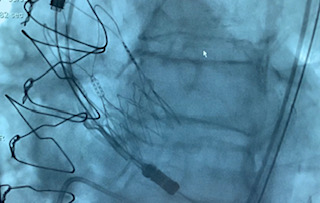

Alliberament d'una TAVI

Alliberament d'un TAV

Alliberament TAVI